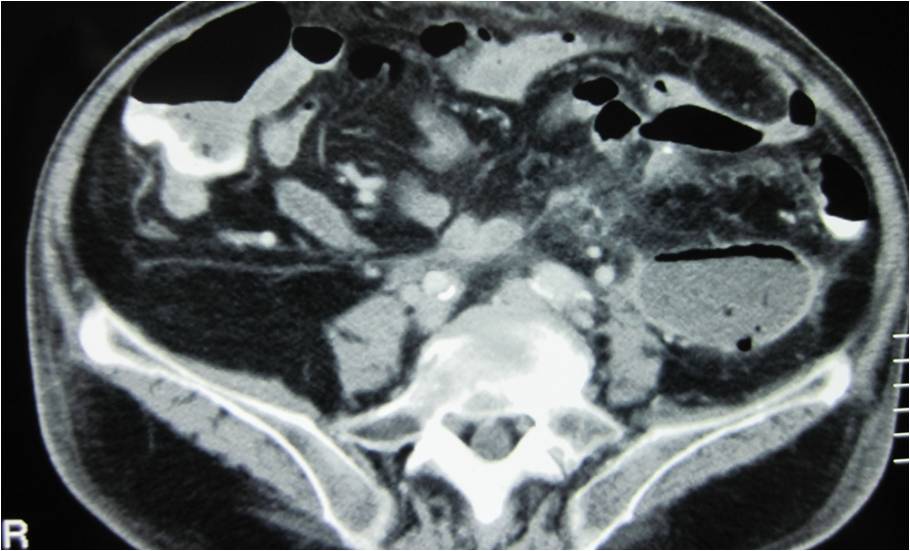

- Abscess post right hemicolectomy

- Successful placement and drainage